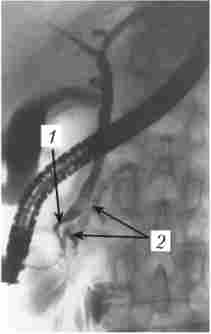

Контрастне дослідження жовчних шляхів (холангіографія) необхідно в першу чергу хворим з біліарним ХП або з підозрою на такий. Вона здійснюється або непрямим методом з пероральним або внутрішньовенним введенням контрастної речовини, який, на жаль, не забезпечує достатню якість знімків і взагалі непридатний у хворих з обтурацією жовчних шляхів, або методом прямого контрастування. Останнє досягається при РХПГ (рис. 20.3), а також за допомогою черезшкірної чреспече- нічний пункції жовчного міхура або жовчної протоки, в тому числі під контролем УЗД, комп'ютерної томографії або лапароскопа.

ретроградна холангіопанкреатографія

Мал. 20.3. Ретроградна холангіопанкреатографія. Контрастували жовчні протоки, жовчний міхур і головний панкреатичний протік. На знімку спостерігаються продовжене звуження (симптом «мишачого хвостика») термінального відділу загальної жовчної протоки (панкреатична частина) і різке розширення головного панкреатичного протоку з нечіткістю його контурів

При блокованому камінням або відсутньому (після холецистектомії) жовчному міхурі можливе введення контрастної речовини шляхом пункції жовчних проток. При наявності жовчного свища контрастування досягається в результаті фістулографії.

На підставі холангиографии можна судити про наявність жовчних конкрементів, розширення, деформації або стенозировании жовчних шляхів, наявності перешкод для відтоку жовчі в дванадцятипалу кишку.

На рентгенограмі можуть бути виявлені характерні для хронічного панкреатиту ознаки: розширення головного панкреатичного протоку (іноді у вигляді контрастною «цінуй озер»), наявність в протоці стриктур, конкрементів, а також сполучених з ним порожнин (псевдокист).

На одночасно здійснюваної холангіограмми може виявлятися стриктура термінальної частини холедоха, розширення поза- і внутріпече- нічних жовчних проток, холедохолітіаз і т. Д. З огляду на можливі ускладнення РХПГ (гострий панкреатит, гострий холангіт аж до розвитку бактеріально-токсичного шоку при наявності інфекції в протоках) , це дослідження виконується в основному за абсолютними показаннями, перед операциию або з одночасною ендоскопічної декомпресією проток і з обов'язковою профілактикою ОП (октреотид, спазмолітики, і фузіонних терапія).